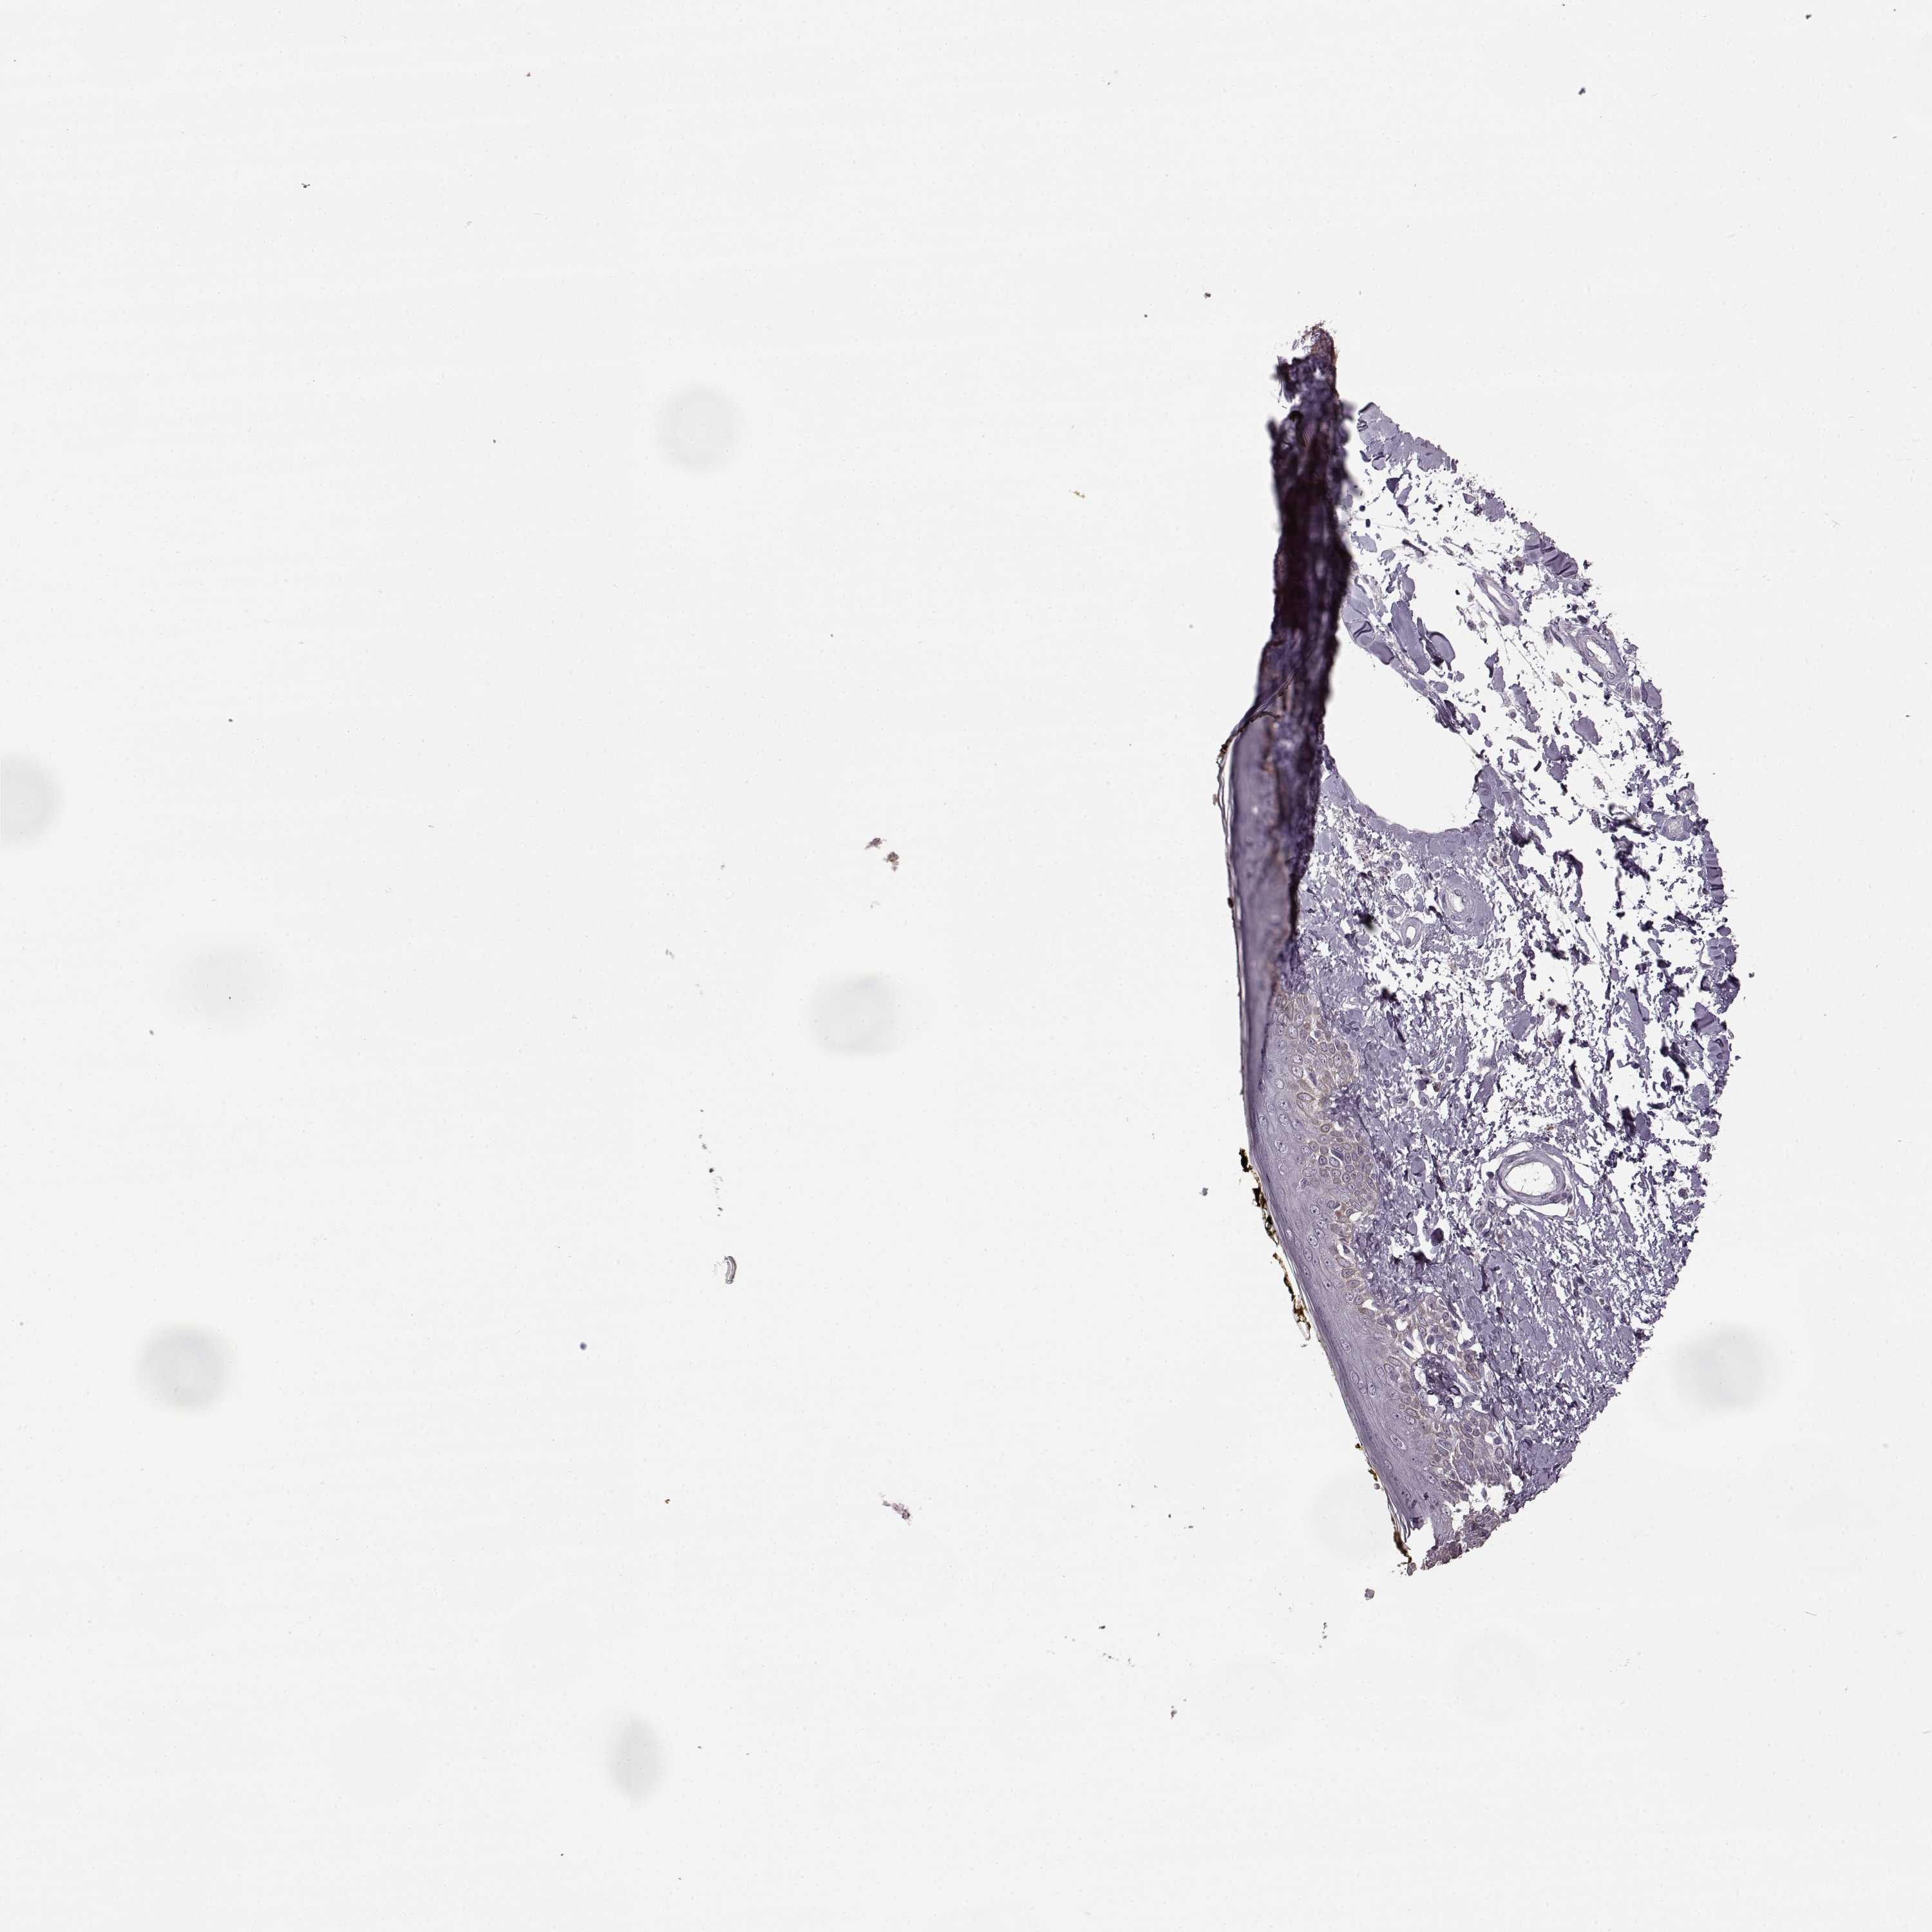

SKIN 2 - Antibody stainingi

Antibody staining in the annotated cell types in the current human tissue is reported as not detected, low, medium, or high, based on conventional immunohistochemistry profiling in selected tissues. This score is based on the combination of the staining intensity and fraction of stained cells.

Each image is clickable and will lead to virtual microscopy that enables deeper exploration of all samples and also displays staining intensity scores, fraction scores and subcellular localization as well as patient and tissue information for each sample.

Antibody HPA023908

Epidermal cells Not detected